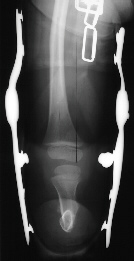

FOLLOW-UP: At 9 years of age the patient was noted to have an increased flexion contracture about the knee with radiographs demonstrating a recurrent valgus deformity. She subsequently underwent a repeat tibial derotational osteotomy with correction of the valgus deformity. Her postoperative course was uncomplicated. Currently she is 17 years old and ambulates well with the use of a custom below-knee PTB prosthesis with a carbon copy foot.